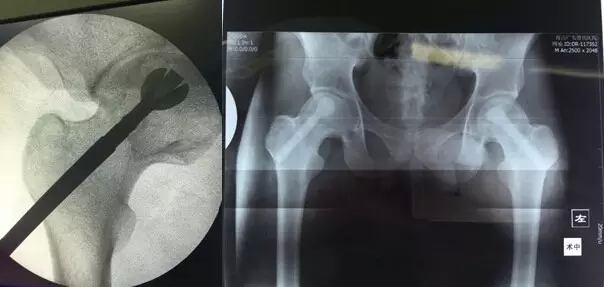

3月29日,舟山廣安醫(yī)院危立軍副院長(zhǎng)為一名29歲的雙側(cè)股骨頭早期壞死患者成功實(shí)施了股骨頭壞死減壓、病灶清除、可注射人工骨植入術(shù)。這是當(dāng)前國(guó)際上在治療此類(lèi)疾病的最先進(jìn)的微創(chuàng)手術(shù)技術(shù)。該項(xiàng)技術(shù)可以有效阻止股骨進(jìn)一步頭壞死而導(dǎo)致關(guān)節(jié)軟骨面塌陷,通過(guò)再造創(chuàng)面誘導(dǎo)骨再生、成骨而達(dá)到治愈目的。

治療股骨頭壞死的關(guān)鍵是終止病變進(jìn)展,在股骨頭壞死的早期階段,保留患者自身髖關(guān)節(jié)具有很高的臨床和社會(huì)價(jià)值。使之有可能往良性的軌道上發(fā)展。廣安醫(yī)院開(kāi)展的“股骨頭壞死減壓、病灶清除、可注射人工骨植入術(shù)”,在保護(hù)已發(fā)生的壞死骨基礎(chǔ)上,同時(shí)通過(guò)生物學(xué)反應(yīng)促進(jìn)骨再生和病變組織修復(fù),有效恢復(fù)承重能力,防止股骨頭變形塌陷。該技術(shù)手術(shù)切口長(zhǎng)約1-2厘米,創(chuàng)傷小,費(fèi)用低,恢復(fù)快,術(shù)后第二天即可出院,門(mén)診治療。